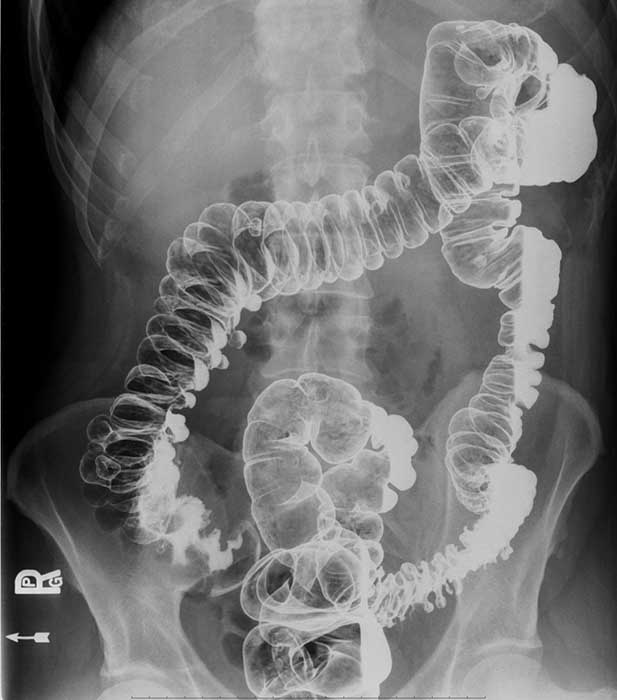

What is volvulus? (twist)

A twisting of a portion of the bowel that may cause obstruction and compromise blood supply.

Where does volvulus most commonly occur?

In the cecum and sigmoid colon. (image shows cecal volvulvus)

How does cecal volvulus occur?

The cecum twists on its long axis and often displaces upward and to the left.

How does sigmoid volvulus occur?

The sigmoid twists on its mesenteric axis, rotating left or right.

Bowel obstruction and compromised blood supply.

What can compromised blood supply lead to in volvulus?

Necrosis and gangrene.

Obstruction can cause severe distension leading to bowel perforation.

What are common symptoms of volvulus?

Severe abdominal pain, vomiting, and abdominal distension.

How is volvulus treated?

Emergency surgery to untwist the bowel.